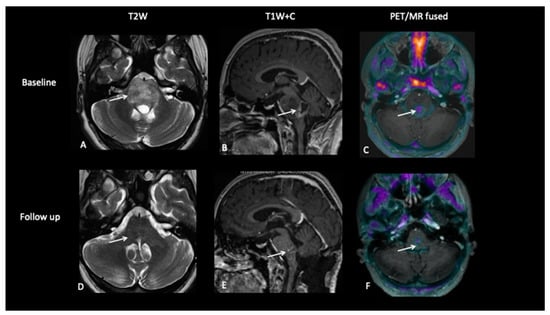

Figure 4.

At baseline, there is a large pontine tumour (A) with a dorsally exophytic enhancing component (B), which shows FCho avidity on the PET/MR fused image (C). Follow-up imaging demonstrates residual dorsal enhancement (D,E), but FCho confirms no avidity (F) consistent with complete metabolic response.

- Patient 1: Diagnostic Biopsy and Radiotherapy Planning

A 16-year-old male presented with a short history of sharp bilateral eye pain that was intermittent in nature. He was seen by an ophthalmologist who detected bilateral swollen optic discs suggestive of papilledema. A diagnostic FCho PET–MRI scan showed an expansile pontine tumour with heterogenous, predominantly high T2-weighted signal abnormality. Choline uptake was seen in the enhancing component (Figure 4). A neuro-navigational stealth-guided biopsy was performed, centred on the choline avid region of the tumour, and the histology confirmed this to be a high-grade astrocytic tumour with a very high proliferative index. A response assessment scan after 6 weeks of chemoradiotherapy showed excellent treatment response with a complete metabolic response.